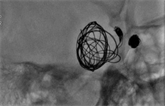

Figure 3. (a) Right carotid-cavernous fistulas secondary to aneurysmal rupture. (b) Endovascular treatment with positioning detachable balloons and coils into the right cavernous sinus. (c) Immediate post-op control.

During that same diagnosis procedure and through the same right femoral artery access, the fistula was catheterized with a microcatheter, interrupting the arterio-venous communication. Endovascular treatment was then performed positioning detachable balloons and coils into the right cavernous sinus. Immediate postoperative control confirmed total occlusion of the fistula (Figure 3(b) & Figure 3(c)).